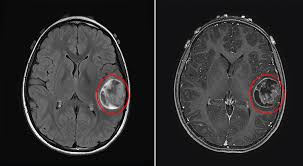

Brain tumours are usually detected using brain imaging, such as a CT scan or MRI scan. MRI scans often provide more detailed information and help the neurosurgical team at NNRC plan further treatment.